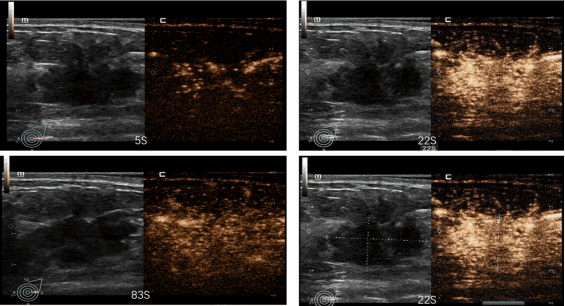

超声造影:应用于肝、甲状腺、乳腺等脏器占位性病变的定性诊断,极大提高了病变的检出率和诊断准确性。

临床特色:1.浅表亚专业组在乳腺和甲状腺疾病的诊断及治疗方面尤为突出。2.利用超声引导下肿物穿刺活检、超声造影及穿刺活检等先进技术,可以进行精细的病理获取和疾病评估。